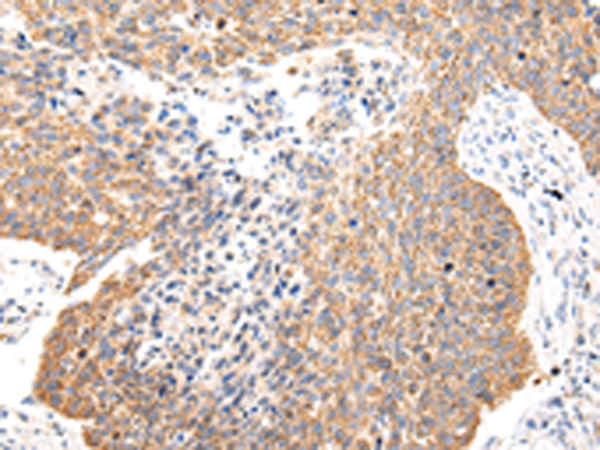

分类: 科研抗体货号: P12454别名: FECD; PPCD; FECD1; PPCD2应用: IHC反应种属: Human, Mouse